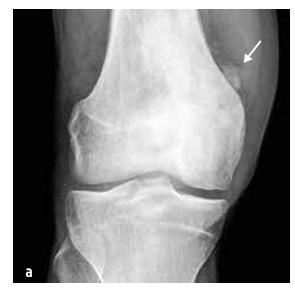

Malignant tumours

In children, the most common types are osteosarcoma (55%, see Figure 5) and Ewing’s sarcoma (35%, see Figure 6), while chondrosarcoma is extremely rare. This group also includes soft tissue sarcomas (rhabdomyosarcoma and non-rhabdomyosarcomas), mesenchymal cell tumours, extraskeletal Ewing’s sarcoma, synovial sarcoma, fibrosarcoma and embryonic sarcoma.

Figure 5

Osteosarcoma of the distal femur